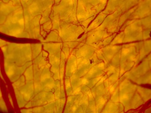

► 激光在生物组织中的传播与能量沉积(蒙特卡洛方法、偏振效应、非傅里叶效应) ► 组织中的生物传热(瞬态脉冲激光作用下的选择性光热效应、多孔介质模型) ► 血管热损伤机理 激光照射前 激光照射后

激光诱发血栓的体外实验

激光诱发血栓的数值模拟

红细胞力学模型

颈动脉建模